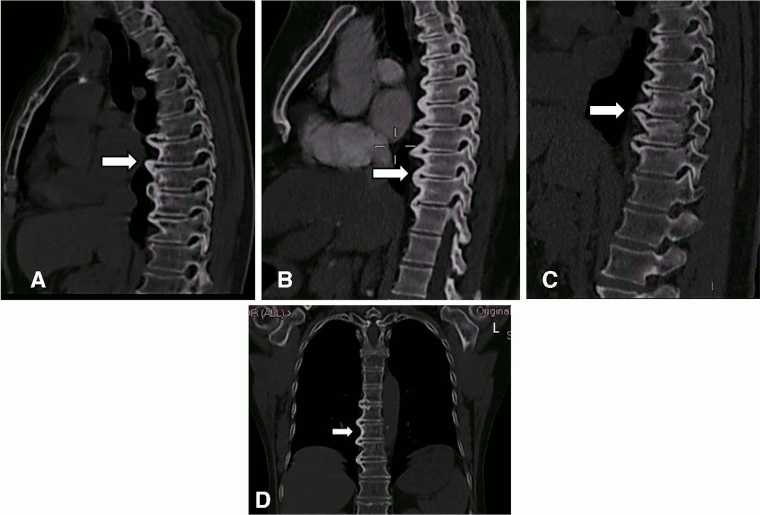

CT images of the thoracic spine in DISH. (A–C) Sagittal: CT scan images of anterior flowing osteophytes (arrows). (D) Coronal: dish of the thoracic spine (arrow) reconstructed from the chest CT scan. L = left

Mader R, et al. RMD Open 2020; 6: e001151. doi: 10.1136; used with permission